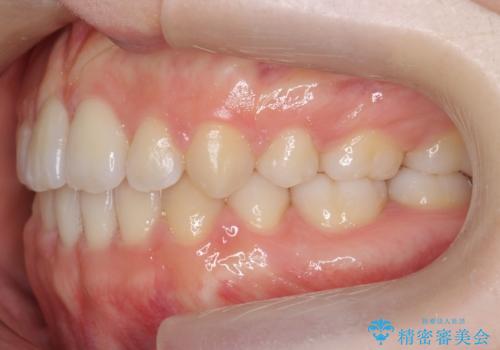

かみ合わせが悪いところを ワイヤー矯正でしっかり治療 マウスピース矯正は難しい症例

前歯、奥歯ともに反対咬合になっており、また上顎の前歯が少し突出気味でした。

時間はかかりましたがしっかりかみ合わせから治すことができました。

口元の突出も改善しており理想的な横顔になりました。